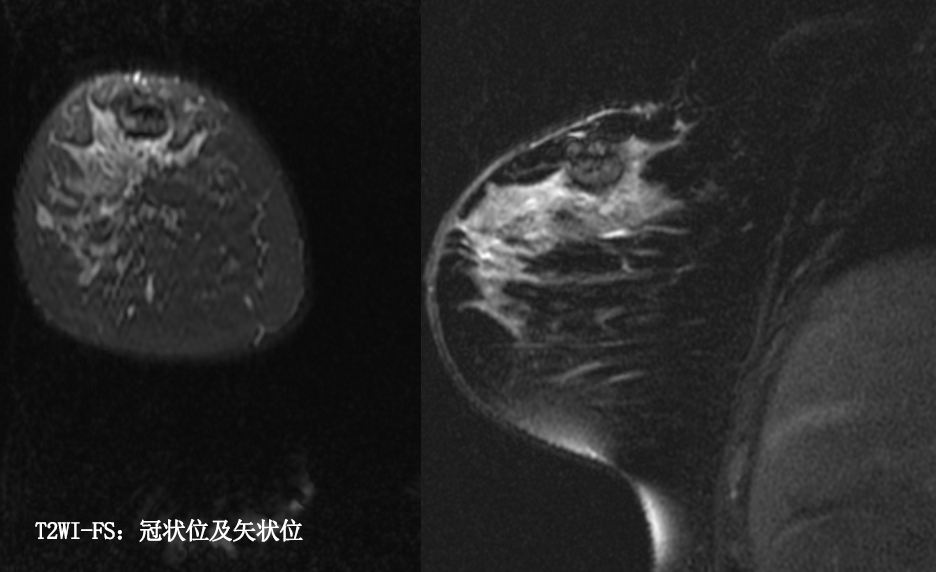

MG/CT: